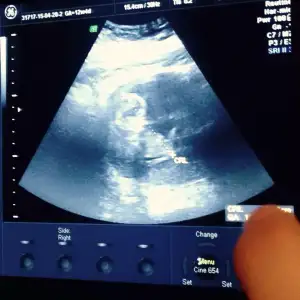

Kiz burda denilen oluyormus fizigim geometrim hep kotuydu benim bu nubtan falan anlamiyorum hayriniza bir yorumlayin cinsiyeti ne olabilir? 12+1 haftalik ultrason bu.